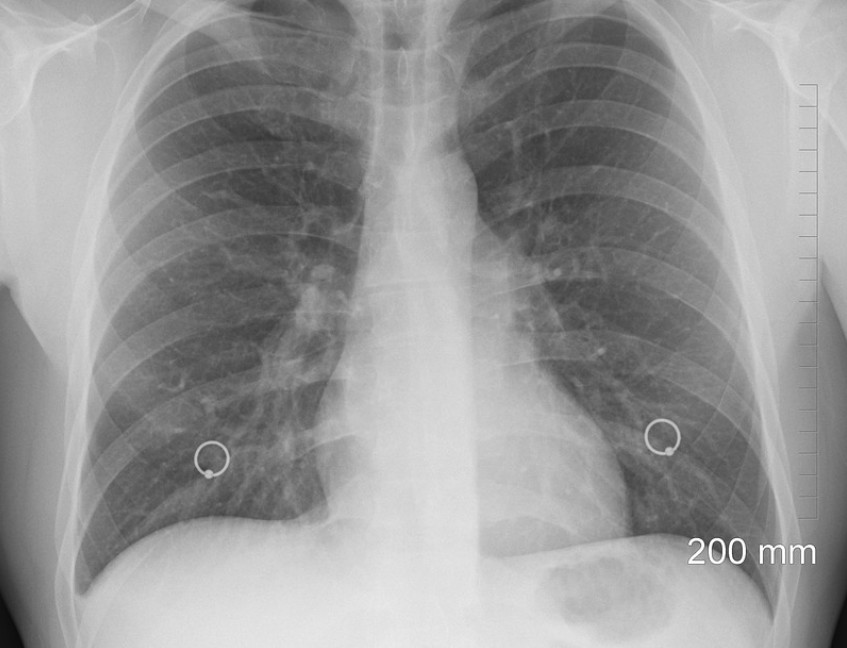

진폐증의 증상으로는 기침, 기침, 숨결, 흉통 등이 있습니다. 폐암의 진단은 일반적으로 흉부 엑스레이, 폐 기능 검사 및 신체 검사의 조합에 의해 수행된다. 폐암 치료법은 없지만, 치료는 질병의 진행을 지연시키고 먼지에 더 이상 노출되는 것을 피할 수 있습니다.